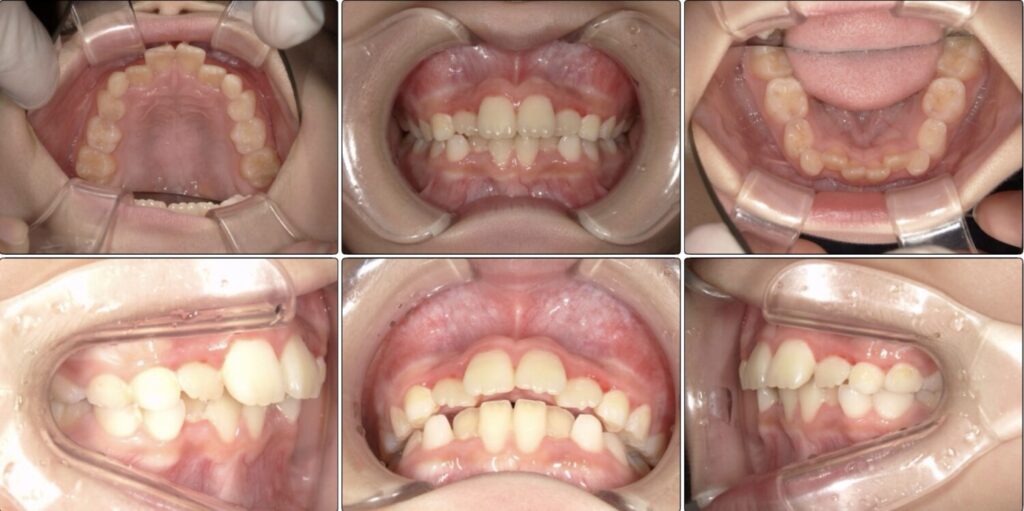

治療前 / 現在

治療開始時

現在

マウスピースとアクティビティーを3ヶ月続けた経過です。

入れなかった歯が少しずつ綺麗に並んでいいアーチになってきています。

上の歯並びの変化

こちらも3ヶ月の経過です。

がたつきがかなり改善しています。

この頃はまだアクティビティーとマウスピースの装着のみです。